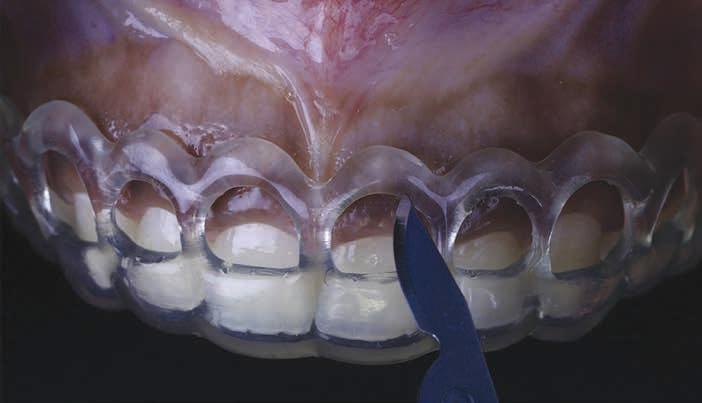

Thevirtualdesignofthesurgicalguideisperformedaccordingly.Dataaretransferredtoa3D printer,andtheguideisprinted.Afterplacingtheguideinthepatient ’smouth,aninternal bevelincisionismadefollowingtheupperborderofthewindowoftheguide(Figure6 ).The

Figure 4 Surgical guide made with tooth-colored acrylic resin placed on teeth.

Figure 6. Surgical incision based on the guide. Reproduced from Alhumaidan A, Alqahtani A, al-Qarni F. 3D-printed surgical guide for crown lengthening based on cone beam computed tomography measurements: a clinical report with 6 months follow up. Appl. Sci. 2020;10(16):5697, CC-BY 4.0. https://doi.org/10.3390/app10165697.39

The virtual design of the surgical guide is performed accordingly. Data are transferred to a 3D printer, and the guide is printed. After placing the guide in the patient’s mouth, an internal bevel incision is made following the upper border of the window of the guide (Figure 6). The guide is then removed, and a second sulcular incision is made. The secondary flap is removed while visualizing the new crown lengths. A full-thickness mucoperiosteal flap is elevated and the surgical guide is then placed again to determine the extent of osteoectomy needed (Figure 7). An osteoectomy is then performed, followed by osteoplasty to finalize buccal bone thickness. The guide is then positioned for a final check before sutures are placed, and hemostasis is ensured.